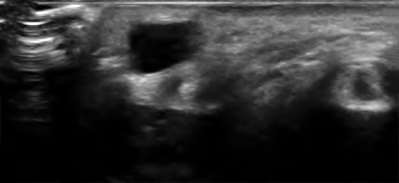

A 20-year-old park ranger trips and falls onto his right wrist with the wrist in extension and pronation. The local urgent care orders both radiographs and a CT, which you review and determine to be normal. The patient complains of ulnar-sided wrist pain. On exam, his tenderness is localized to the fovea. Ulnar deviation also causes him pain. There is no snapping sensation with wrist supination, flexion, and ulnar deviation. He otherwise has 5/5 strength to his first dorsal interosseous muscle with 4mm static two-point discrimination on the ulnar side of the 4th digit. Which of the following injuries is most likely responsible for his symptoms and exam?